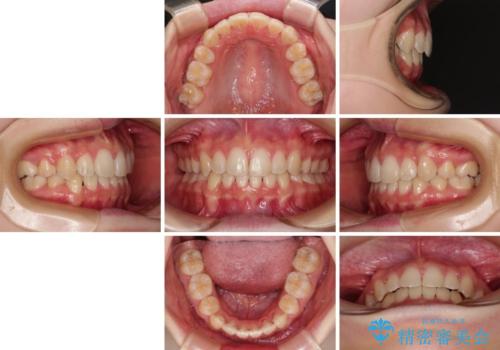

- 口元の閉じにくさを気にして来院された患者様です。

上下ともに歯列が前方に突出していたため、上下左右の第一小臼歯4本を抜去し、ワイヤー装置による矯正治療を行うこととしました。

上下左右4本抜歯する場合には、通常2年から2年半ほどの期間を要しますが、舌のトレーニングをしっかりと行っていただいたことで、1年9ヶ月で終了することができました。